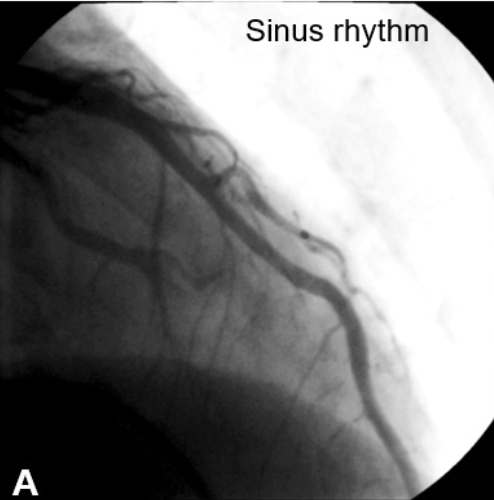

An electrophysiological study (EPS) was performed and atrial flutter (AFL) was induced similar to the initial ECG. Because his presenting symptom was angina, the patient was referred for coronary angiography at this point to rule out significant coronary disease. No significant coronary lesions were detected; however, a myocardial bridge was noted in the mid left anterior descending artery (mLAD) (Figures 2A and 2B). As the patient’s symptoms were combined with tachycardia, coronary angiography was repeated with concurrent EPS. During induced tachycardia, persistent compression and near total obstruction of the mLAD were seen (Figures 2C and 2D), and the patient complained of severe angina similar to his initial episode. Catheter ablation of the AFL was successfully completed, and at the 8-month follow-up visit, the patient remained free from both chest pain and palpitations.